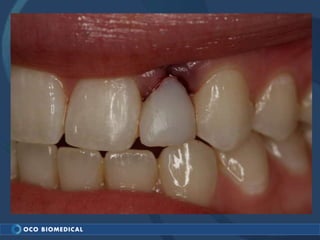

A 3.0mm dental implant was placed to replace congenitally missing maxillary lateral incisors. Dr. Tim Kosinski used a 1.8mm pilot bur and tissue punch to prepare the osteotomy site, then placed the implant by hand and seated it with a torque wrench. After ensuring the implant trajectory was within the restorative envelope, an acrylic coping was placed for temporary fabrication. At the 1 week post-op appointment, excellent soft tissue response and papilla formation were observed, and a final impression was taken to send to the lab for crown fabrication.